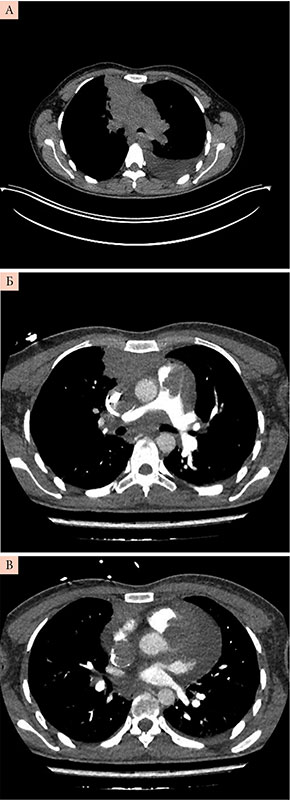

Рис. 3. Компьютерная томограмма органов грудной клетки с контрастным усилением. А, Б, В – разные срезы

Этап 3 – компьютерная томография (КТ) и онконастороженность. В стационарных условиях выполнена КТ органов грудной клетки с внутривенным контрастированием для исключения ТЭЛА (рис. 3). Описано объемное образование примерными размерами до 64 × 32 × 103 мм в переднем верхнем средостении с распространением в S3 правого легкого и вероятностью вовлечения перикарда. В структуре образования открывается просвет субсегментарных бронхов S3 справа. Гиповентиляция базальных отделов легких. Утолщение междолькового интерстиция в обоих легких, на этом фоне определяются нечеткие субсолидные очаги субплеврально с обеих сторон. Трахея, крупные бронхи проходимы. Состояние после установки центрального венозного катетера, дистальный конец катетера в просвете ВПВ. Дефект контрастирования просвета ВПВ протяженностью до 65 мм. Дефект контрастирования просвета легочного ствола протяженностью до 46 мм. Скопление выпота в полости перикарда толщиной слоя до 32 мм. Внутригрудные лимфоузлы не дифференцируются. Выпот в плевральных полостях не определяется. Аксиллярные лимфоузлы не увеличены. «Свежих» костных травматических изменений в зоне контрастирования не выявлено.